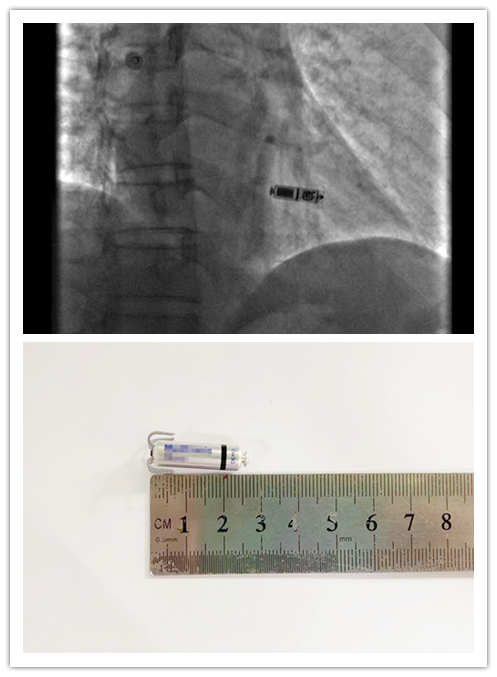

医护人员成功为患者植入双腔无导线心脏起搏器

被植入的起搏器只有胶囊大小

要解除这一“不定时炸弹”,同时又满足患者对生活质量以及手术伤口小,不影响日常生活工作的要求,在综合分析了患者病情和充分考虑患者及其家属意愿后,心内五病区主任容志毅副主任医师周柳荣及团队决定为患者植入一枚只有维生素胶囊大小的双腔无导线起搏器(Micra AV)。9月16日,容志毅、周柳荣医疗团队成功为李先生植入双腔无导线起搏器,手术顺利结束,患者术后反应良好。9月19日,患者顺利出院。

“心脏起搏器就像一个微型电源,每当心脏跳动太过于缓慢的时候,就会释放电流,让心脏恢复正常跳动。”容志毅主任表示,与传统起搏器相比,无导线起搏器仅有维生素胶囊大小,不到2克重,体积和重量为传统起搏器的十分之一,创伤微小,无需切开皮肤、制作囊袋,无需经颈胸部血管放置电极导线,仅通过股静脉小小穿刺点直接植入到心脏,能避免手术切口疤痕,手术时间短,术后两天就能恢复正常的工作和生活,大大降低了传统起搏器并发症的发生率,且弥补传统起搏器植入后患者不能做核磁共振检查的情况,能更多患者感受到精准医疗带来的益处,成为患者“心”福祉。